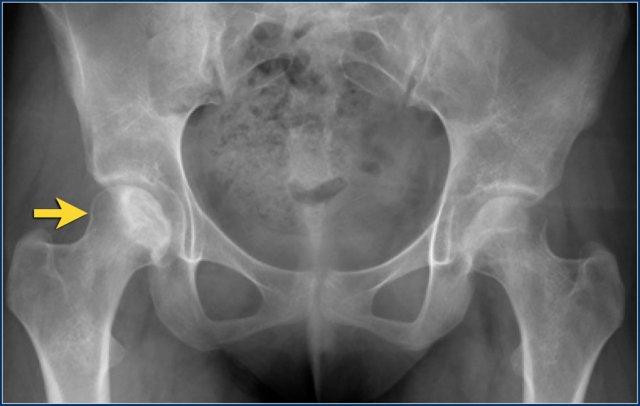

Phim X-quang của một bệnh nhân 15 tuổi mắc bệnh bạch cầu lympho cấp tính được điều trị bằng corticosteroid.

Hình ảnh đơn thuần không thể phân biệt với bệnh Perthes, nhưng dựa trên thông tin lâm sàng, đây là hoại tử vô mạch thứ phát.